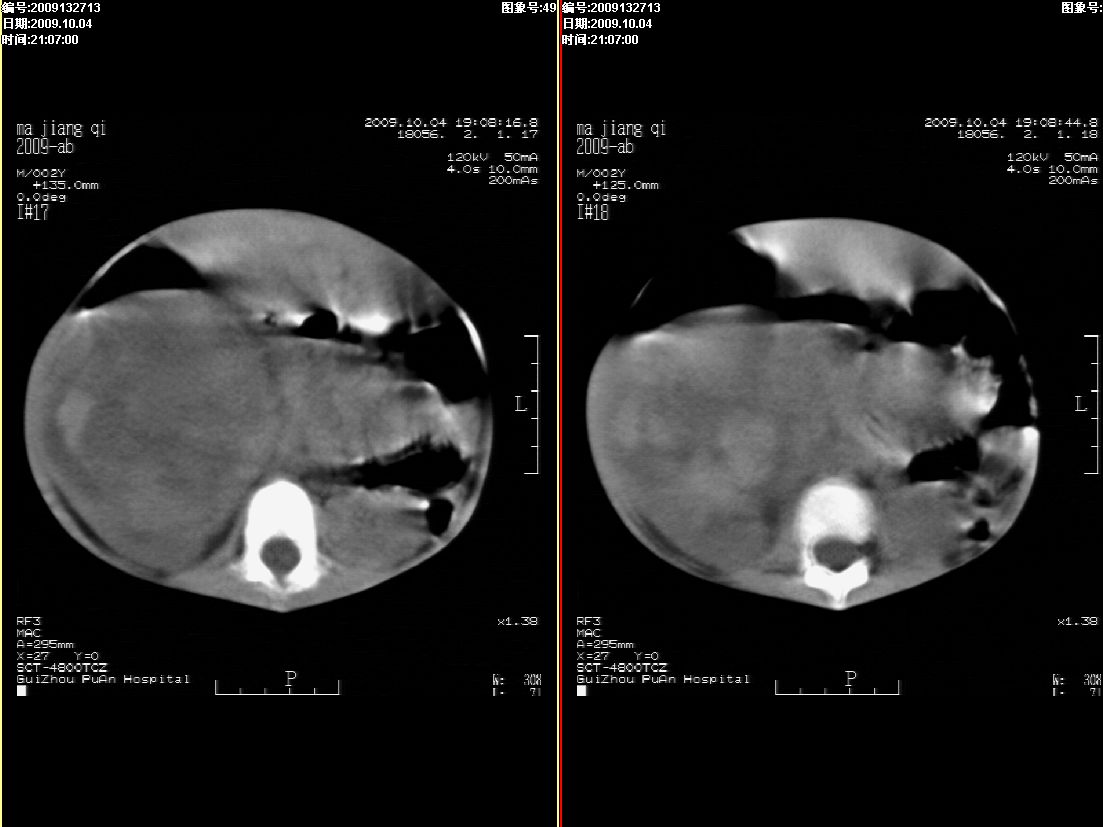

右肾巨大囊性占位病变,其内密度不均,正常肾结构消失,肝脏,肾上腺及肠管等受压移位。双肺内多发大小不等的结节及块状影。考虑右肾母细胞瘤伴双肺多发转移。

肾母细胞瘤(wilms),系儿童最常见的恶性肿瘤,好发于3岁以下儿童,瘤体较大,主要由胚胎性肉瘤样细胞和上皮样细胞构成,临床以腹部肿块;血尿和高血压为主要体征。

ct表现:密度不均匀的大肿块存在;出血和坏死。与神母鉴别点:wilms易向颅脑转移,而神母易往肺转移。

ct表现:密度不均匀的大肿块存在;出血和坏死。与神母鉴别点:wilms易向肺转移。而神母易往颅脑转移.